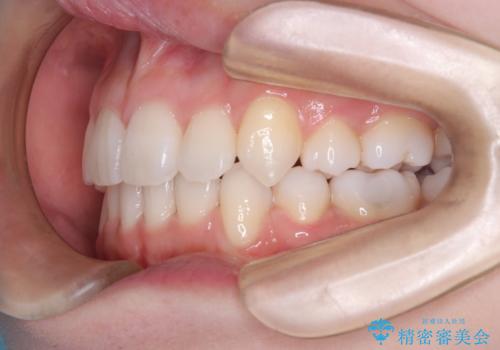

【審美ワイヤー】八重歯を治したい。

- 左上の犬歯の凸凹や正中のずれを主訴に来院されました。

凸凹を治すために、上下左右の小臼歯を抜歯してワイヤー矯正を行いました。

患者様には、顎間ゴムを使用していただくことで、2年という期間で治療を終了することができました。